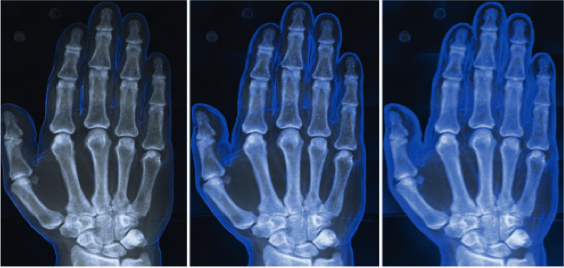

Pin On Juniper Publishers Journal Of Orthopedic Orthoplastic Surgery Jojoos